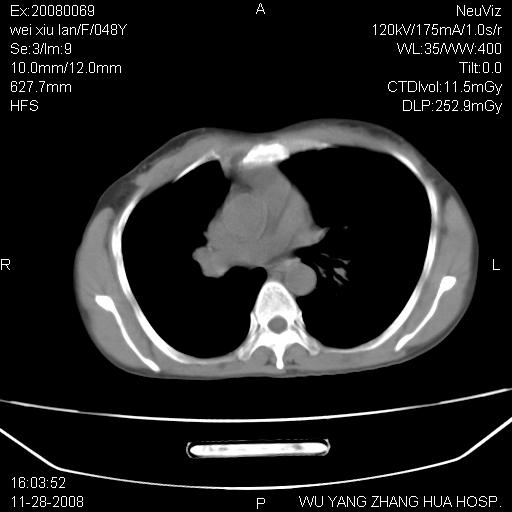

标题: CT16847:女,48岁,咳嗽,发热两日,平常偶有上腹部不适。 [打印本页]

标题: CT16847:女,48岁,咳嗽,发热两日,平常偶有上腹部不适。

能否考虑食管裂孔疝?请老师们多多指教。

这个是左侧膈膨升伴不完全性胃翻转,手术将松弛的左横膈膜折叠缝合即解决问题。

支持左侧膈疝,心脏受压右移.

胃、脾脏及部分肠管明显升高,并压迫心脏移位,

首先考虑:左侧膈疝。

左侧胸腔内见胃肠及脾脏影

支持膈疝

左膈顶及肋膈角均上移,膈面光滑,考虑左膈肌麻痹